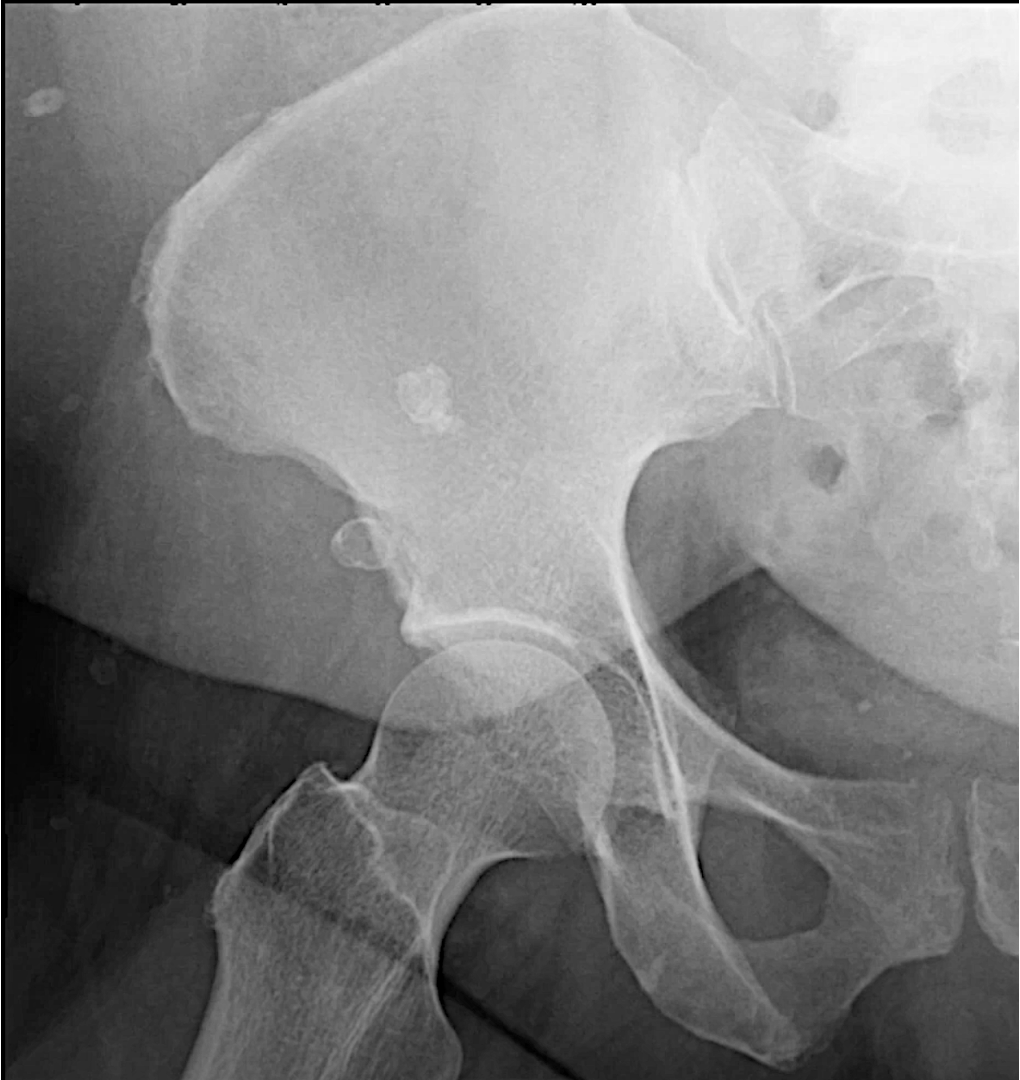

What is an abdominal aortic aneurysm (AAA)?

-enlargement of abdominal aorta

-Risk factors: HTN, atherosclerosis

-usually asymptomatic, but can cause pain

-large ones can rupture lead to hypotension and death

What is a calcified aortic aneurysm?

-common in those with DM and atherosclerosis

-aorta has rim like calcifications

-aneurysm is when normal diameter exceeds 50% of normal size